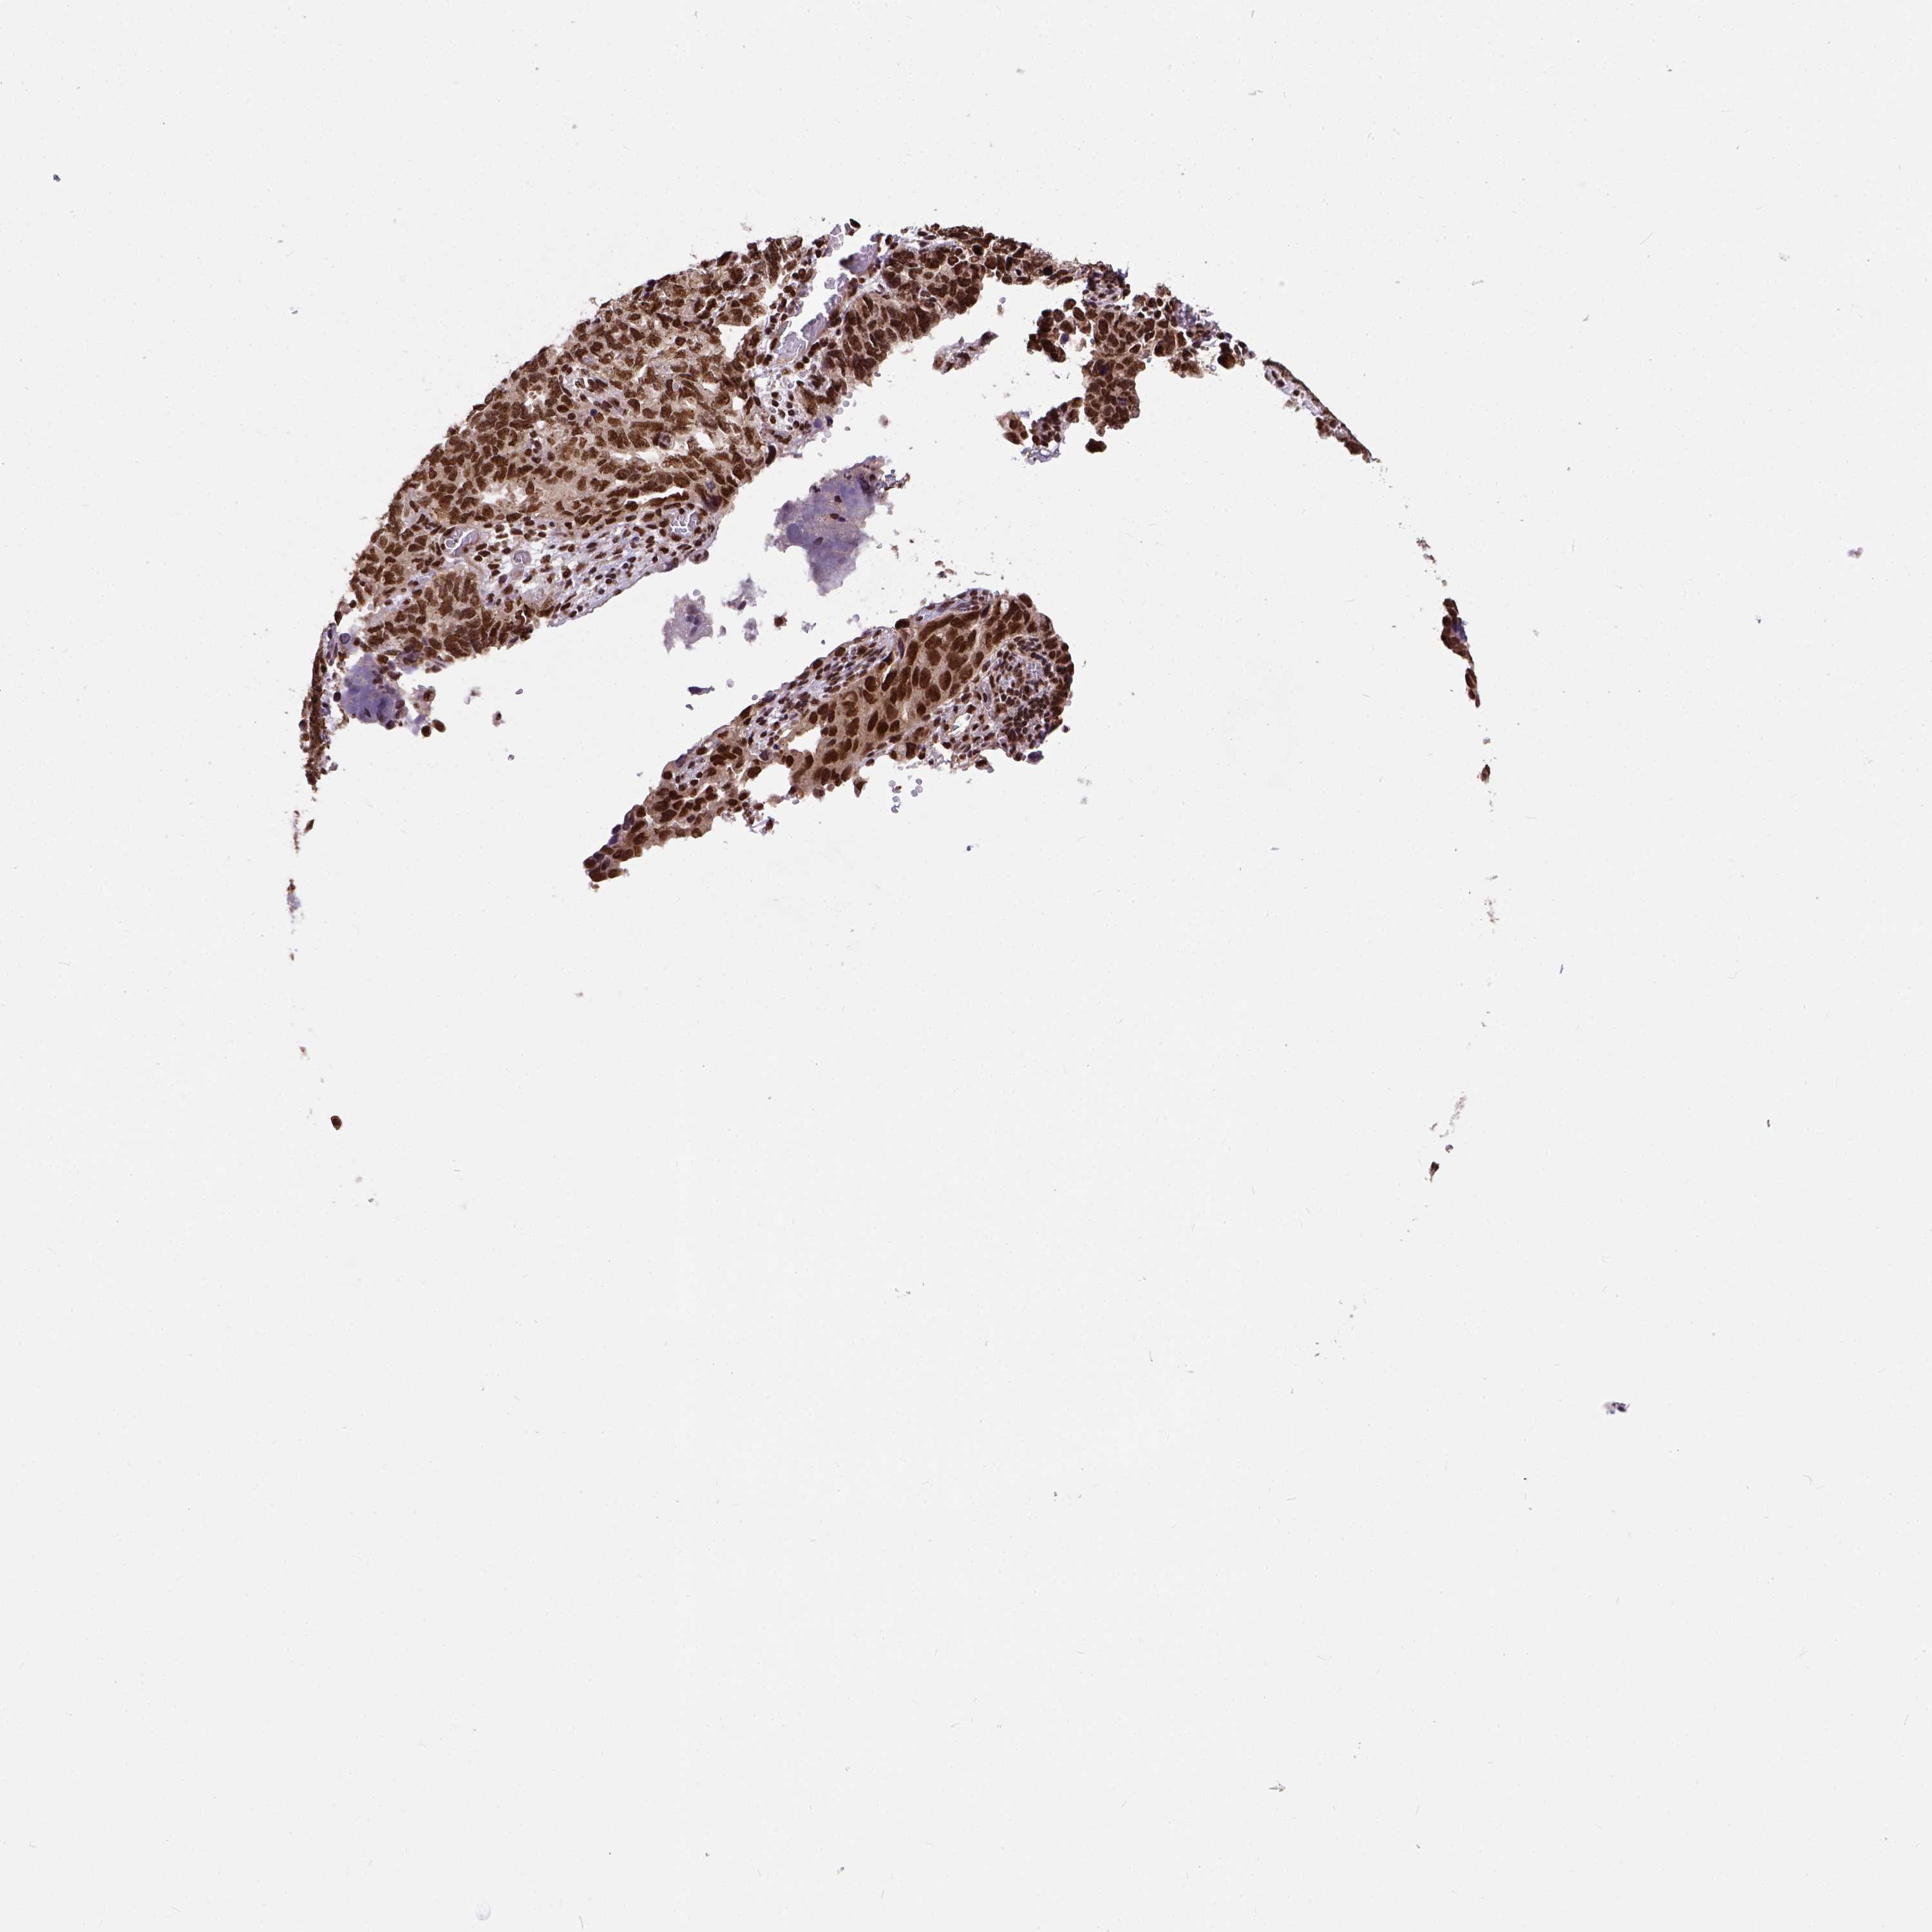

OVARIAN CANCER - Protein expressioni

A mouse-over function shows sample information and annotation data. Click on an image to view it in a full screen mode. Samples can be filtered based on level of antibody staining by selecting one or several of the following categories: high, medium, low and not detected. The assay and annotation is described here.

Note that samples used for immunohistochemistry by the Human Protein Atlas do not correspond to samples in the TCGA dataset.

Antibody stainingi

Antibody staining in the annotated cell types in the current human tissue is reported as not detected, low, medium, or high, based on conventional immunohistochemistry profiling in selected tissues. This score is based on the combination of the staining intensity and fraction of stained cells.

Each image is clickable and will lead to virtual microscopy that enables deeper exploration of all samples and also displays staining intensity scores, fraction scores and subcellular localization as well as patient and tissue information for each sample.

Antibody HPA021238

Antibody HPA062245

Antibody CAB069927

Staining

High

Medium

Low

Not detected

Intensity

Strong

Moderate

Weak

Negative

Quantity

>75%

75%-25%

<25%

None

Location

Nuclear

Cytoplasmic/membranous

Cytoplasmic/membranous,nuclear

Cystadenocarcinoma, serous, NOS

Cystadenocarcinoma, mucinous, NOS

Carcinoma, endometroid